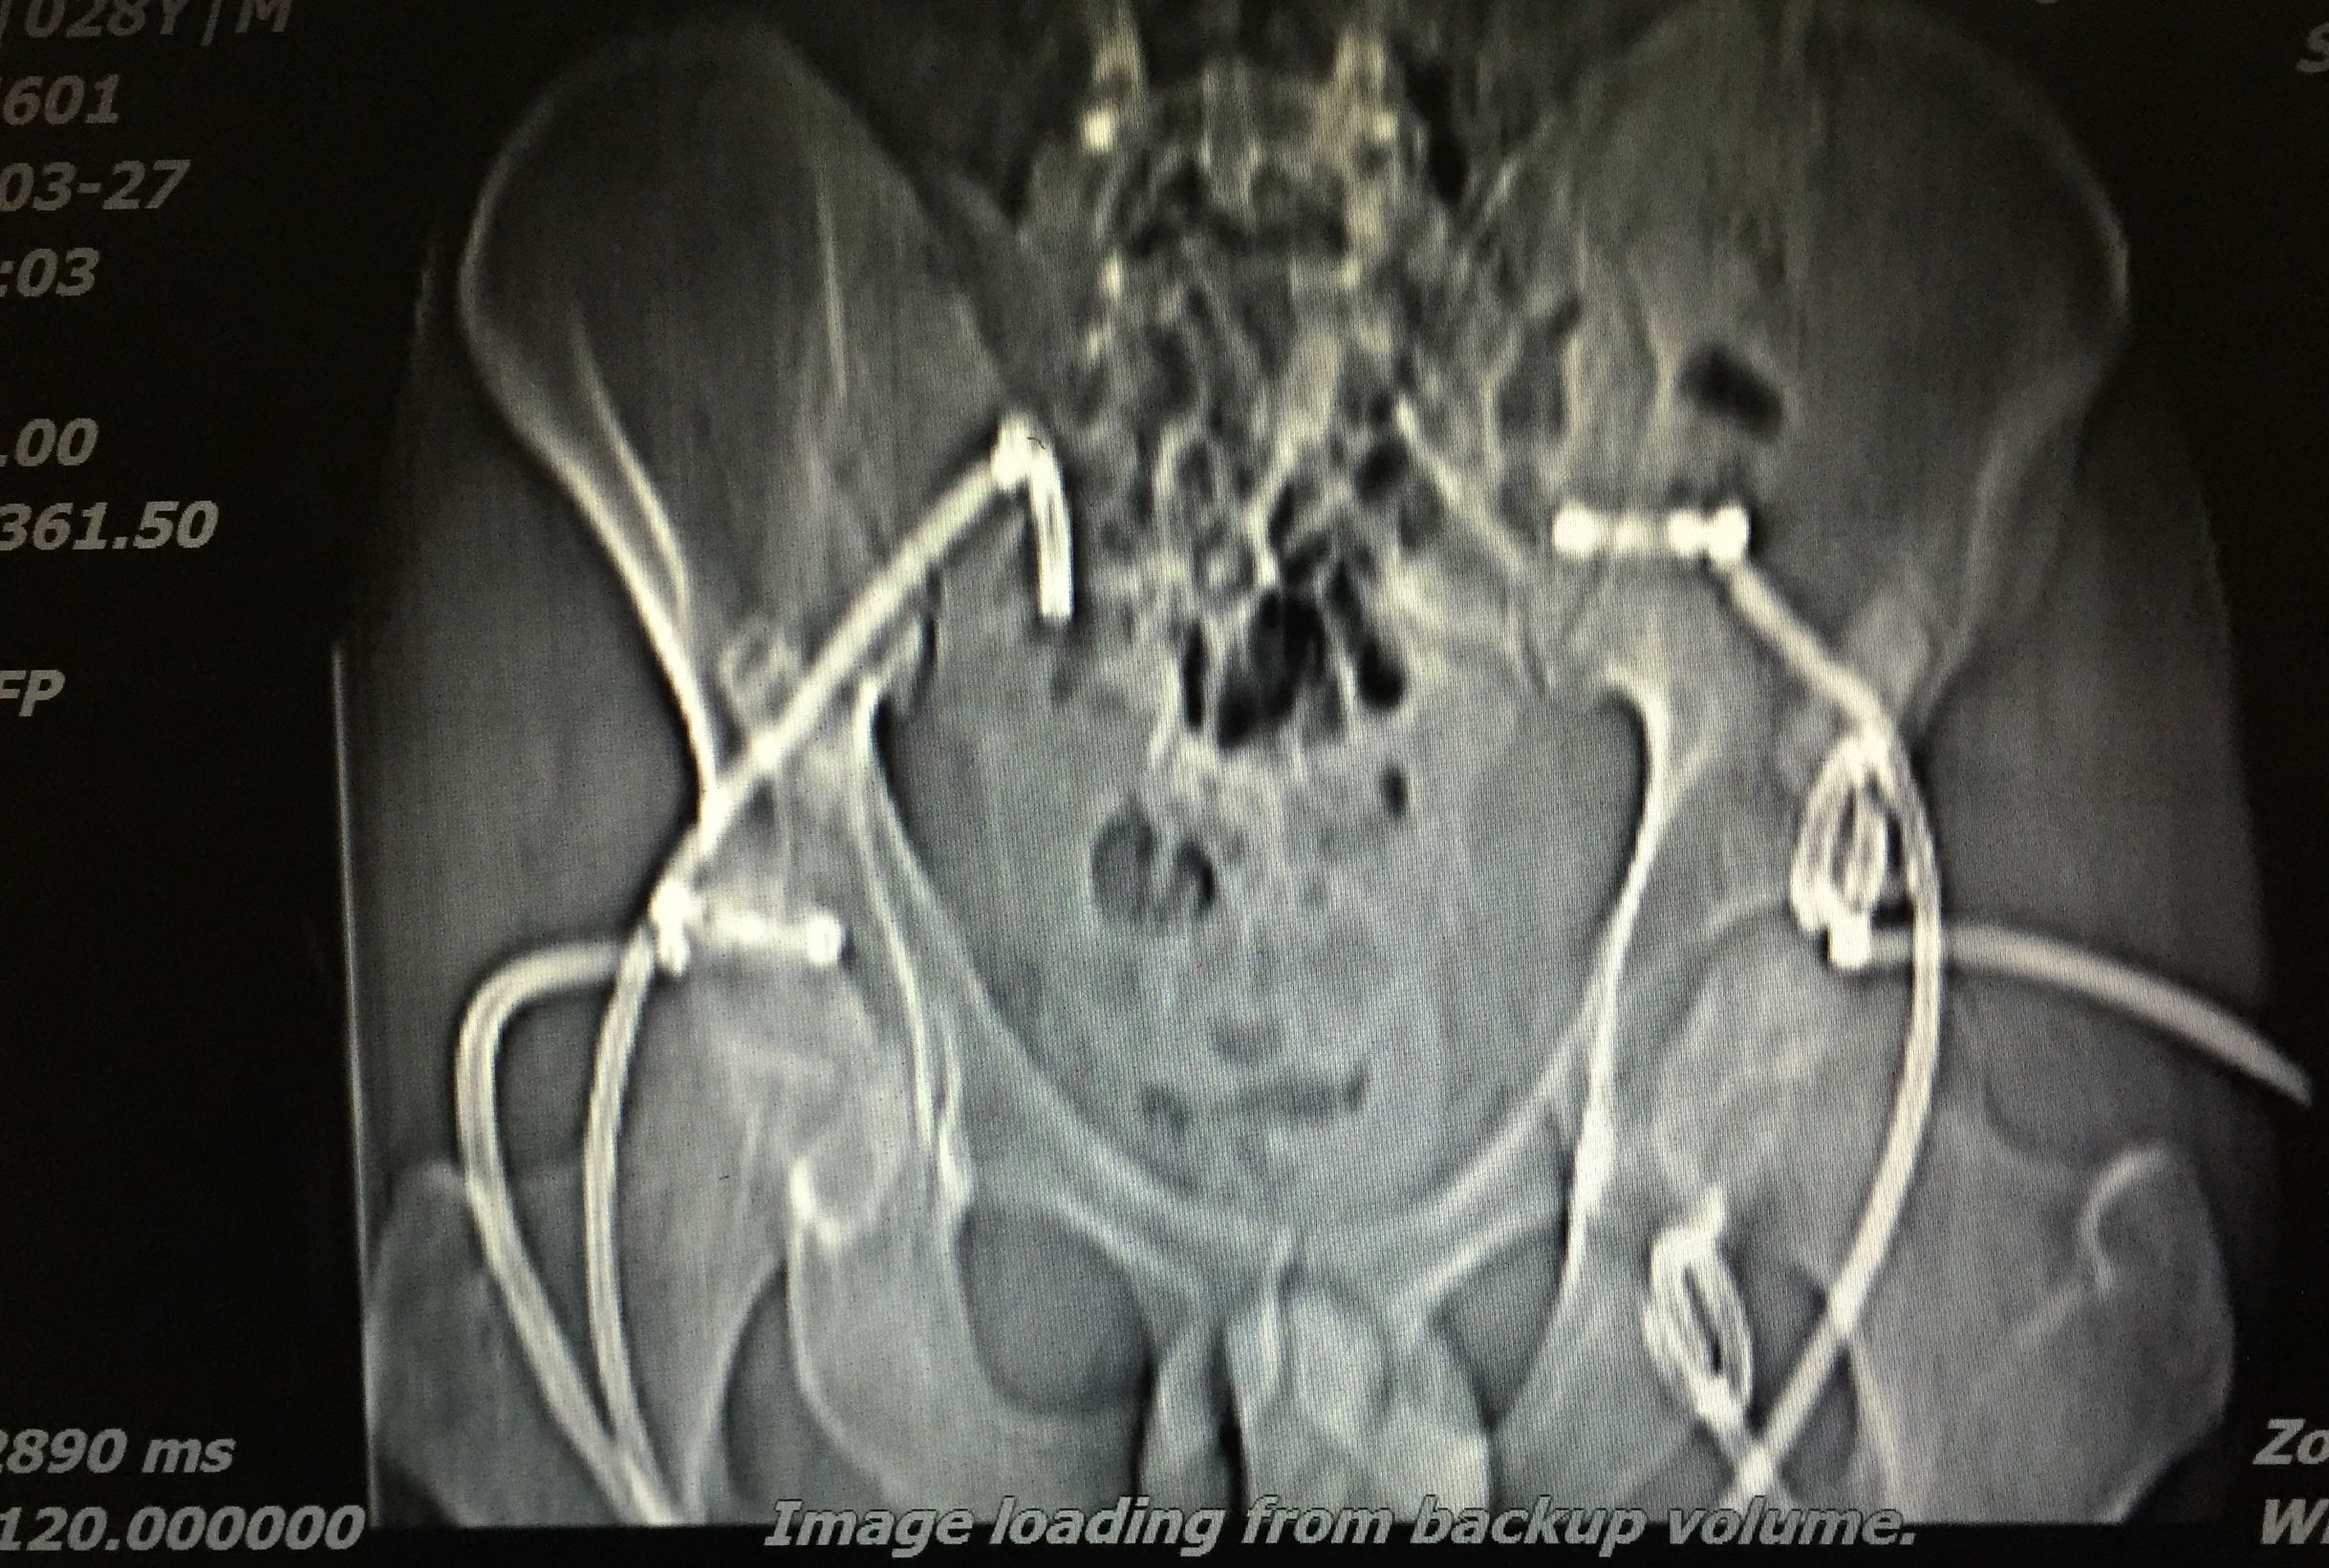

在门诊进行CT引导下穿刺引流术,植入五根引流管(如图白色条状物)

植入一月后,拔出两个引流管,剩余三根引流管仍有脓液溢出。

三月后患者全部拔出引流管。继续抗痨治疗

PS:结核脓肿出现,若能充分引流,可缩短预后时间。CT引导下穿刺引流是各部位脓肿引流较好的处理方案,微创、经济、患者耐受、门诊进行处理。